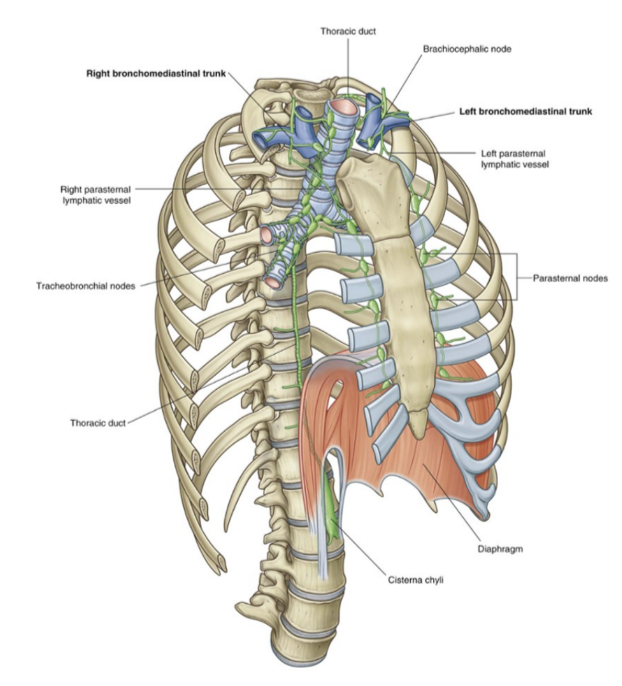

Lymphatic drainage

Venous lymphatics found in the lungs (superficial, subpleural, and deep) all drain into tracheobronchial nodes which are located around the roots of the lobar & main bronchi as well as the trachea (on the sides)

These lymph nodes extend from within the lung, through the hilum & root, and into the posterior mediastinum

Efferent vessels from these nodes — pass superiorly along trachea to unite with similar vessels originating from parasternal & brachiocephalic nodes

These ndes are found anteirorly to the veins of the same name in the superior mediastinum

This coming together of vessels causes formation of right & left bronchomedastinal trunks —

Directly drain into deep veins of the neck or into the right lymphatic trunk (or thoracic duct)